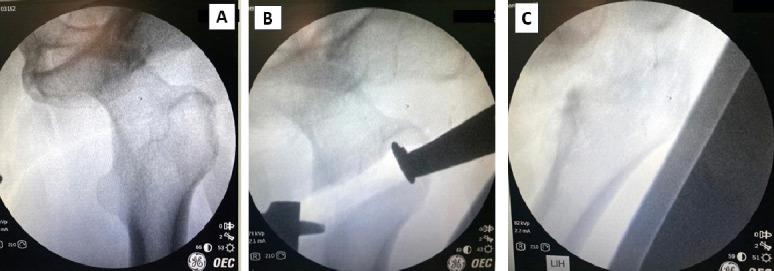

We describe the case of a 49-year-old male who presented to our hospital with a neglected anterior dislocation of the hip. The patient disclosed a history of hip trauma 8 months ago, initially receiving conservative management. However, due to persistent pain and functional limitations, he sought further medical attention. A physical examination, radiographic evaluation, and computed tomography (CT) scan confirmed the diagnosis. The patient underwent THA using dual anterior and posterior approaches, followed by a comprehensive rehabilitation program.

我们描述了一名49岁男性患者的病例,他因被忽视的前髋关节脱位前来我院就诊。患者透露8个月前有髋关节创伤史,最初接受了保守治疗。然而,由于持续疼痛和功能受限,他寻求进一步治疗。体格检查、影像学评估和计算机断层扫描(CT)证实了诊断。患者采用前后联合双入路接受了全髋关节置换术,随后进行了全面的康复计划。